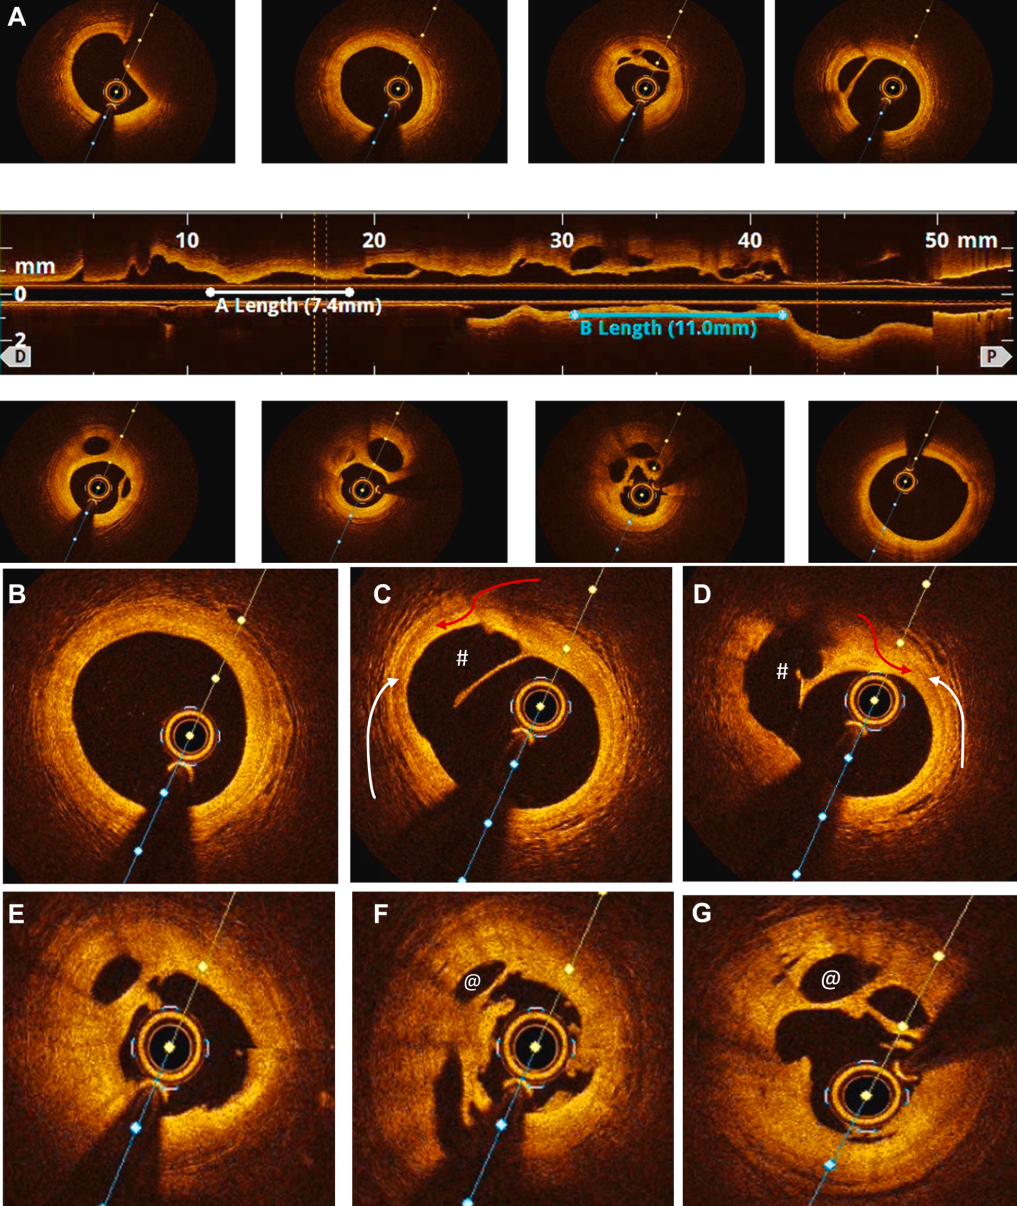

图3 病例1:LAD 和 LCX 支架植入前OCT图像

(A)LAD:壁内血肿(∗)、内膜破裂(蓝色箭头)以及管腔被向内推挤。(B)LCX 显示第二个管腔朝向9点至3点钟方向形成(∗),真腔(#)被推向3点至6点钟方向;可见清晰的内膜破口(蓝色箭头)。

随后,对LAD(图3A)和LCX(图3B)进行分期OCT检查,证实了 SCAD,显示出内膜及内弹性膜破裂、壁内血肿和真腔受压(在造影上表现轻微或被遗漏)。OCT 显示 LCX 存在第二个管腔,真腔推移,并有清晰的内膜撕裂。基于OCT诊断,患者随后接受了LCX和近端LAD的PCI治疗。

图5 病例2:右冠状动脉(RCA)支架植入前 OCT 图像

(A)纵向模式OC显示血栓复杂的通道化特征。(B-G)放大 OCT清晰显示血栓内的通道(∗),以及其后方完整的内弹力膜(红色箭头)和中膜(空心箭头),确认了病变的腔内性质而非血管壁内的夹层。第二个管腔后方完整的内弹力膜轨迹证实它位于血管腔内,提示为血栓而非自发性冠状动脉夹层(SCAD);血栓的边缘(#)可以追溯到由于血栓再通形成的次级管腔(@)(不要与 SCAD 的假腔混淆)。

后续的OCT检查揭示了真相(图5):在一个机化的管腔内结构中,存在多个细小不规则通道,符合血栓再通的特征,而无任何SCAD迹象。这促使我们启动了抗血栓治疗并进行了PCI。该病例凸显了造影误诊的风险以及OCT在实现诊断精确性方面的关键作用。